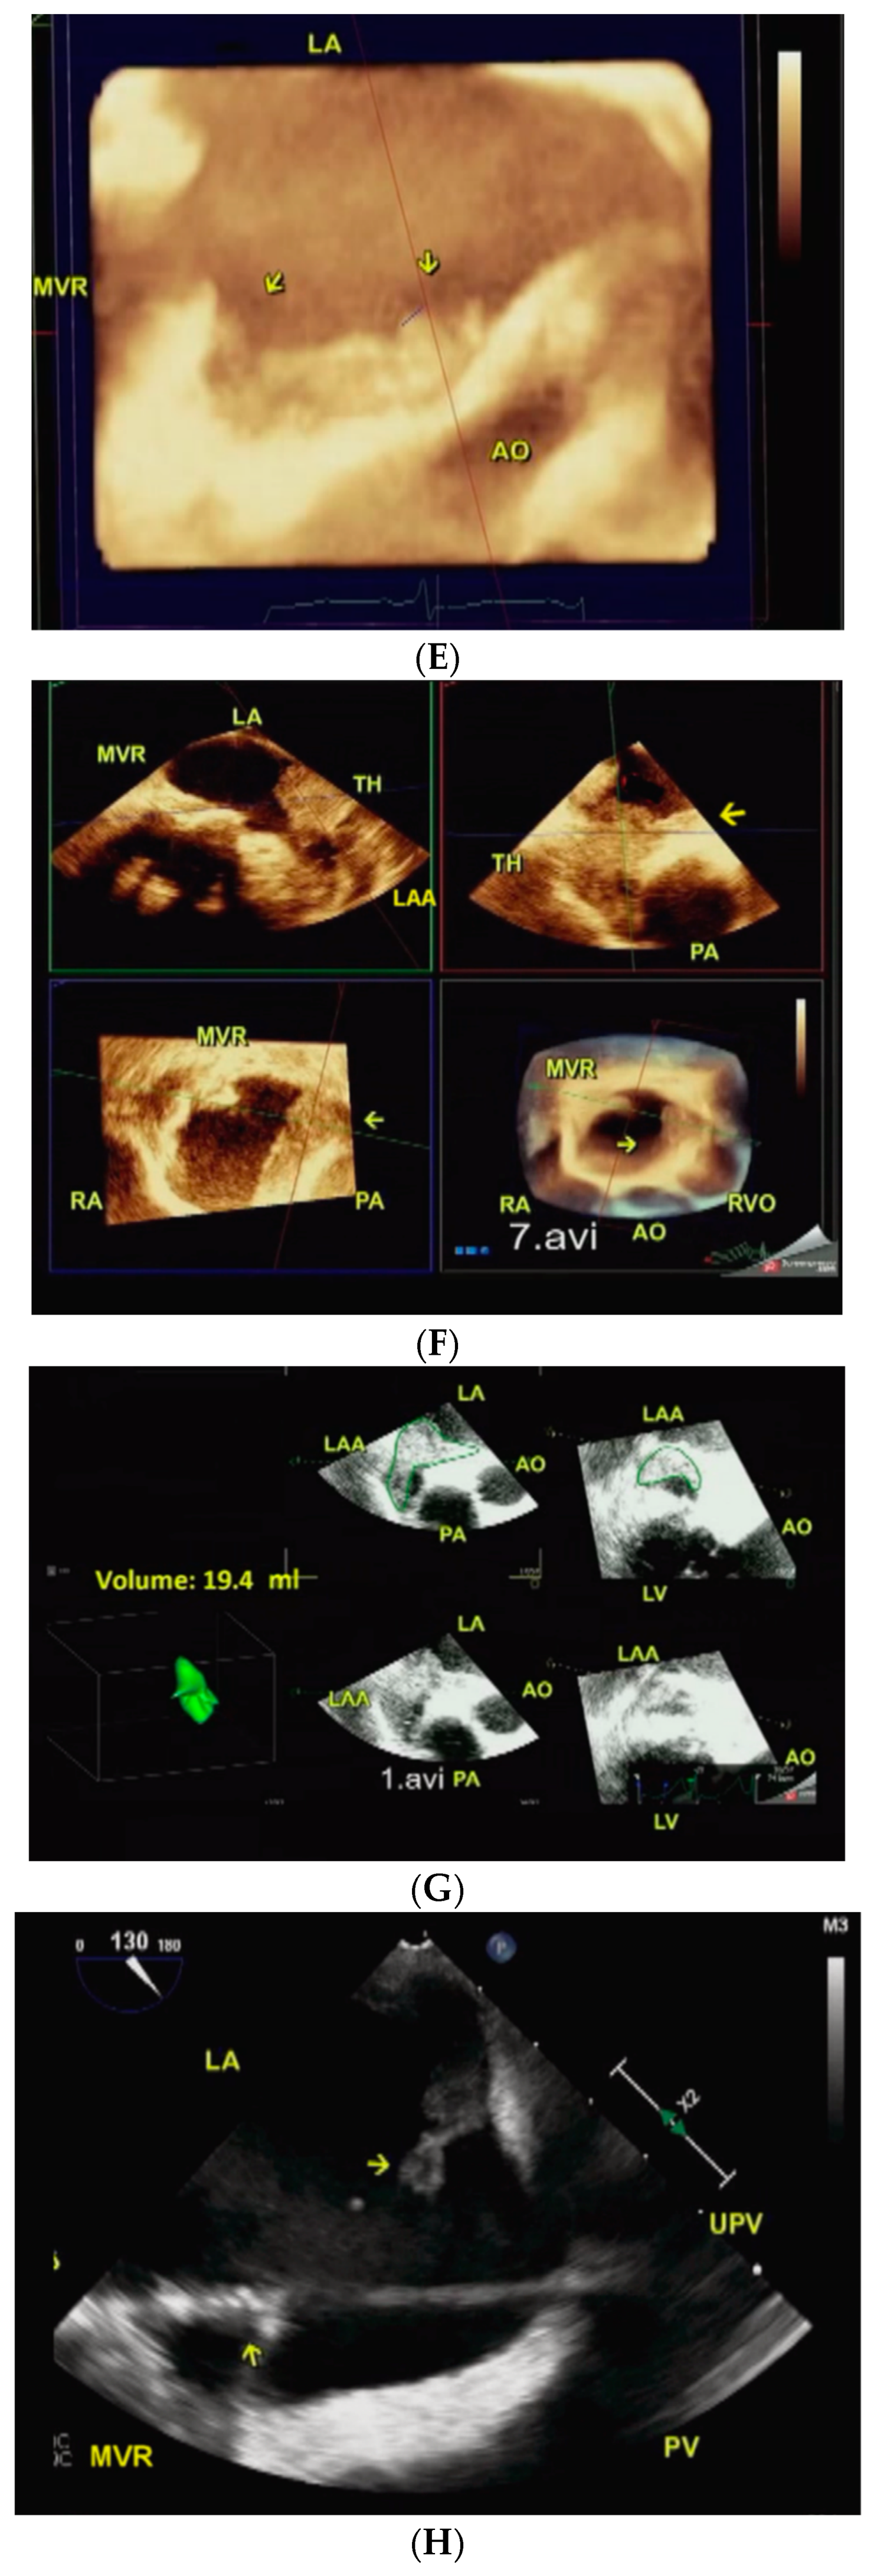

Figure 3. (AC). The same patient (Case 2 above) returned 2 years and 8 months later with severe stenosis of the new MVR. Pre-procedure. Two-dimensional transesophageal echocardiography (A). A much smaller and poorly organized residual confined to LAA is noted in A. Live/real-time three-dimensional transesophageal echocardiography with color Doppler (B). The MVR orifice (red arrow) viewed in MPR mode in B measures 0.68 cm2 by direct planimetry indicative of severe restenosis. Post-procedure. Live/real-time three-dimensional transesophageal echocardiography (C). A short-axis view in full volume mode shows all the three MVR rings in C. # 1 points to the outermost ring of the original surgically implanted MVR. # 2 shows the middle ring of the first transcatheter implanted MVR. # 3 demonstrates the innermost ring of the second transcatheter implanted MVR. Abbreviations as in previous Figures.